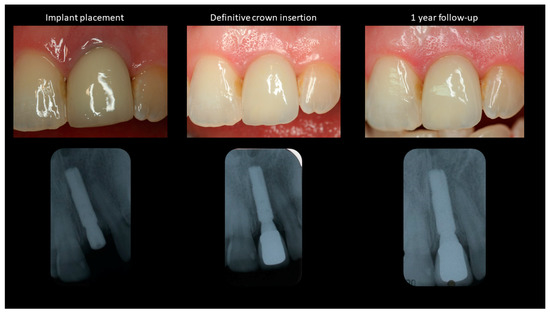

- T0—Baseline/Implant placement.

- T1—Definitive crown placement.

- T2—1-year follow-up.

| Soft Tissue Recession (in mm) | Bone Level Changes (in mm) | PES * | ||||

|---|---|---|---|---|---|---|

| Mesial Papilla | Midfacial | Distal Papilla | Mesial | Distal | ||

| T0 | - | - | - | - | - | 10 |

| T1 | 0.2 | −0.2 | 0.0 | 0 | 0 | 12 |

| T2 | 0.2 | −0.2 | 0.1 | −0.2 | −0.2 | 12 |